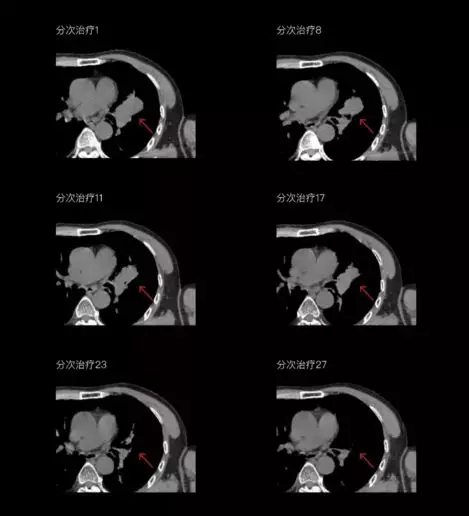

一體化CT-linac讓自適應(yīng)放療ART概念變?yōu)楝F(xiàn)實(shí)?;颊呷煶虪顟B(tài)監(jiān)控,適時(shí)在線調(diào)整治療計(jì)劃,精準(zhǔn)控制治療劑量,為患者動(dòng)態(tài)定制個(gè)體化治療方案。uAI賦能智能勾畫和自動(dòng)計(jì)劃,秒級勾勒靶區(qū)和危及器官,大幅縮短自適應(yīng)放療時(shí)間。

聯(lián)影CT-linac全程監(jiān)測治療過程病灶的變化,及時(shí)調(diào)整和優(yōu)化治療方案